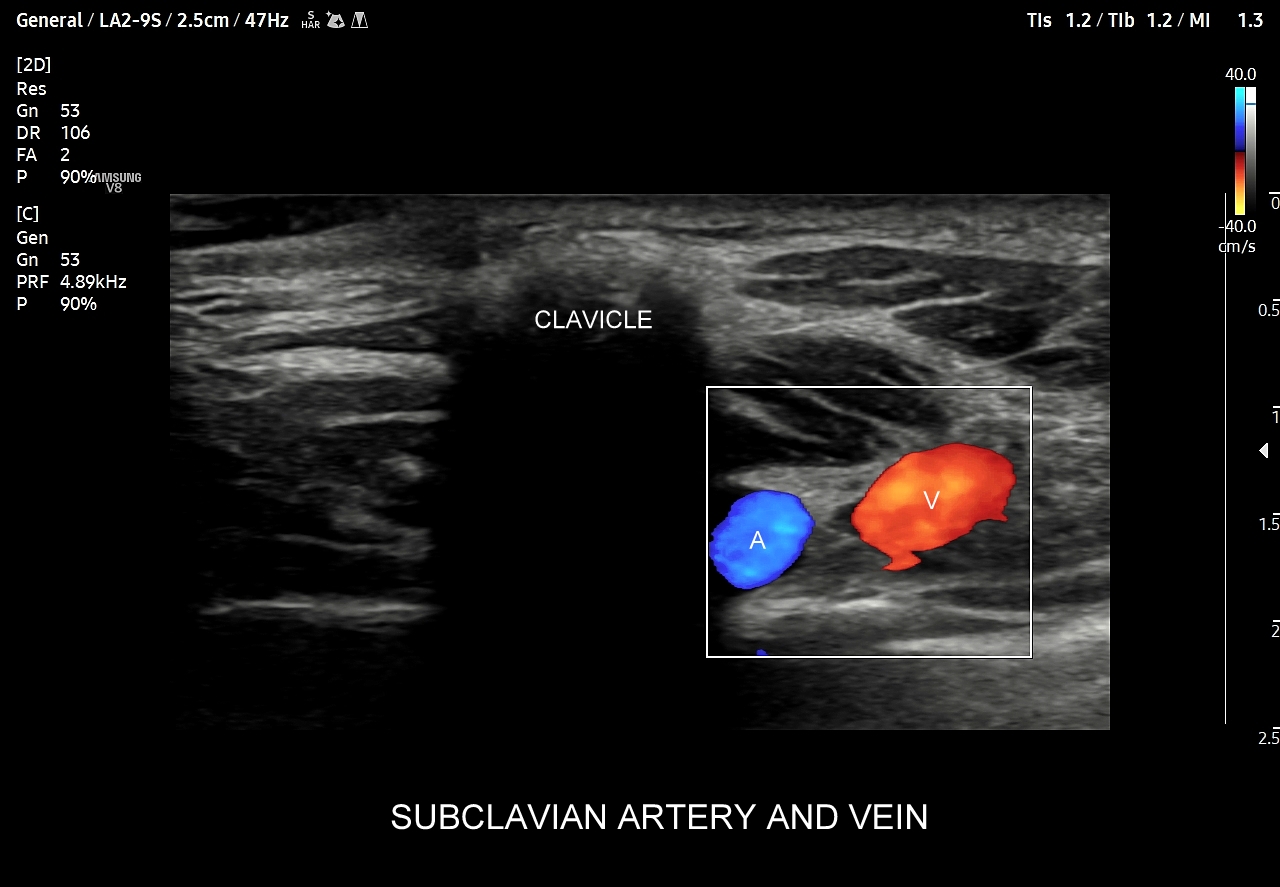

W praktyce tryb Dopplera pulsacyjnego łączy się jednoczasowo z trybem Dopplera kodowanego kolorem w zestaw nazywany obrazowaniem duplex-Doppler. Takie połączenie dwóch trybów obrazowania na jednym ekranie pozwala badającemu na zebranie szerokiego zakresu informacji kardio-angiologicznych, w tym morfologii naczynia, obecności przepływu, kierunku przepływu, prędkości przepływu, przyspieszenia fali skurczowej, charakteru przepływu, zaburzeń przepływu, przedziałów czasowych, rytmu serca.

Okienko spektralne na wykresie Dopplera spektralnego może zaniknąć w przypadku następujących ustawień technicznych aparatu w trakcie przeprowadzania badania: 1/ objęcie bramką dopplerowską całej średnicy naczynia, 2/ zbyt niskiego ustawienia PRF. Z kolei czynniki biologiczne związane z badanym organizmem, które powodują zanikanie okienka spektralnego to 1/ wystąpienie zjawiska separacji warstwy granicznej (ang. boundry layer separation); 2/ zaburzenia laminarności przepływu (ang. disturbed flow) w naczyniu lub 3/ wystąpienie przepływu turbulentnego. Zjawiska separacji warstwy granicznej oraz zaburzenia laminarności przepływu występują w warunkach fizjologicznych w okolicach podziałów lub odejść tętnic, w poszerzeniach tętnic oraz przy zagięciach naczyń. Z kolei w przypadku patologicznego zjawiska w postaci zwężenia naczynia w pierwszej kolejności występuje zaburzenia laminarności przepływu, a następnie przy nasileniu stenozy dochodzi do pojawienia się przepływu turbulentnego. Opisane powyżej zjawiska dotyczące przepływu krwi poza Dopplerem pulsacyjnym ocenia się również w trybie Dopplera kodowanego kolorem, a najoptymalniej w obrazowaniu typu duplex.